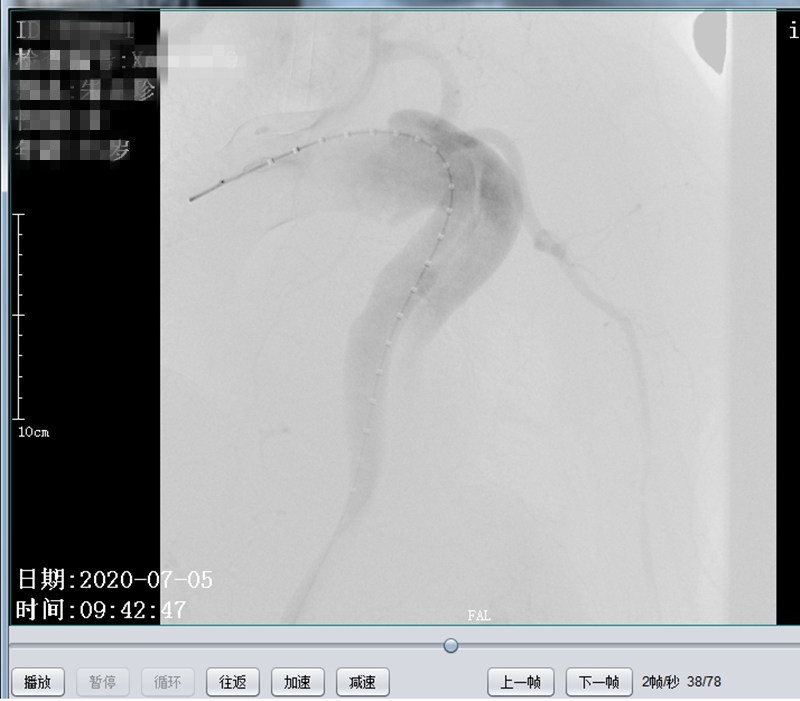

患者朱某,女,72岁,家住我县全军乡,6月22日下午突发胸背部剧痛至我院急诊科就诊,行胸部CTA检查考虑主动脉夹层(Debakey  III型),急请我科会诊。会诊后以主动脉夹层收住介入科,积极给予稳定血压、镇痛治疗。因该患者为先天性失聪失语,沟通十分困难、不畅,祝国臣副主任通过患者女儿耐心与患者沟通,详细询问病情,仔细检查患者体征,并与患者家属说明患者的病情与风险,患者家属了解病情后,十分感激祝国臣医生,决定手术治疗。我科积极完善相关术前准备及手术所需材料,于 7月5日在DSA下行“主动脉、左锁骨下动脉造影+分支型覆膜支架腔内隔绝术”,术中患者破口及真假腔显示明确,破口位置与左锁骨下动脉距离较近,给手术带来一定的困难,根据患者术中造影情况,制定详细手术方案,既保证覆膜支架安全成功释放,又保证不影响左锁骨下动脉血供。术后患者病情平稳,现患者血压、心率稳定,患者胸背部疼痛症状消失。

术中造影明确真假腔位置及与周围大血管关系

术后造影假腔消失,左锁骨下动脉显示良好,支架周围未见造影剂外溢(内瘘)征象